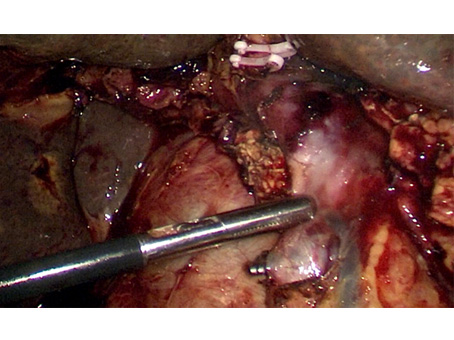

We have state of the art operating theatre with advanced surgical equipments. We have a Karl Storz Spies advanced HD laparoscopy operating system in addition to a 3 chip laparoscopy. We have installed advanced vessel sealing devices like Gen 11 harmonic scalpel, Ligasure from Valley Lab & Argon plasma coagulator. There is a recent addition of Cavitron Ultrasonic Aspirator (CUSA) system into our surgical armamentarium. We have the most recent powered Echelon endo-stapling devices. In addition to all these we have a constant supply of various types of advanced stapling devices for GI surgeries. Our endoscopy machines are having high definition with FICE Technology. Last but not the least we have semi flexible Ureteroscopy for managing common bile duct stones.

CAVITRON ULTRASONIC ASPIRATOR USED FOR LIVER RESECTION

LIVER RESECTION DONE USING CUSA